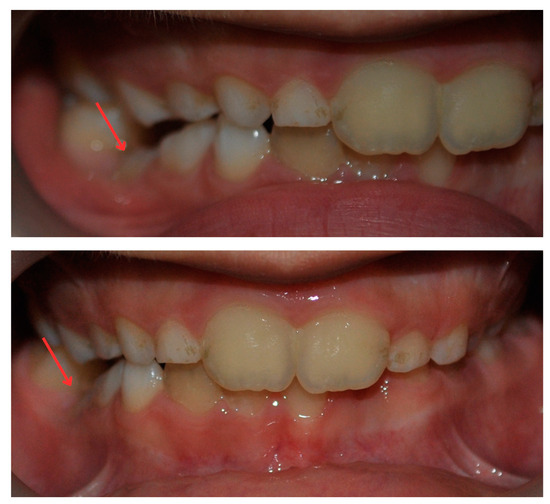

2.3. Treatment Progress